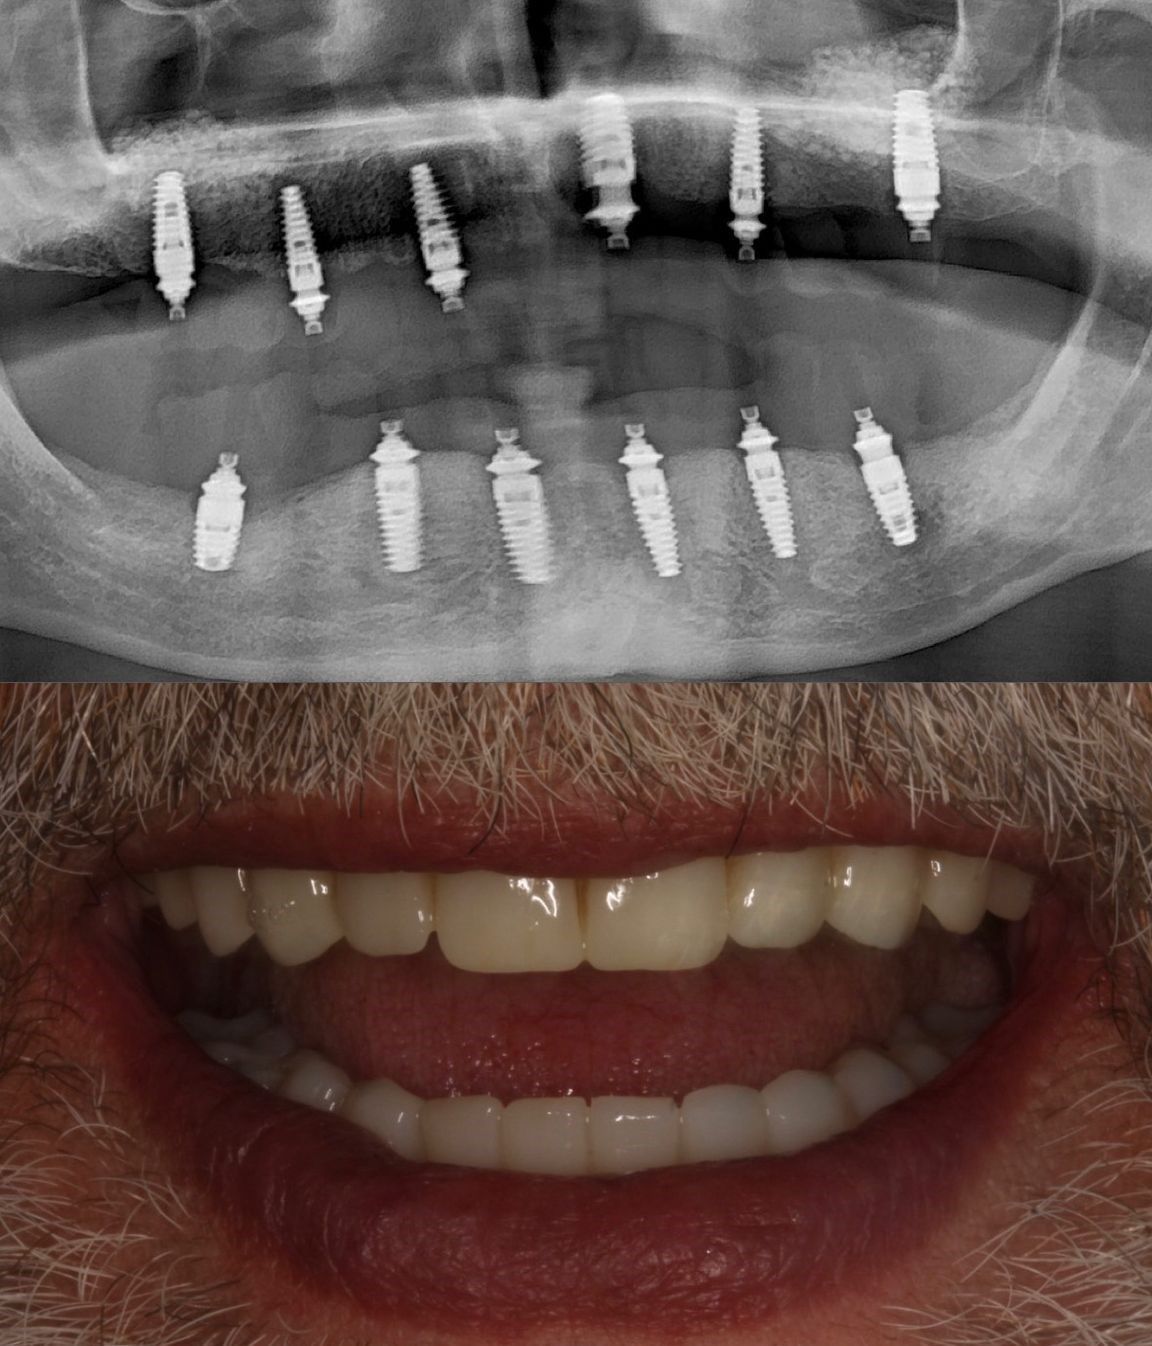

PRÓTESIS SOBRE IMPLANTES SUPERIOR E INFERIOR